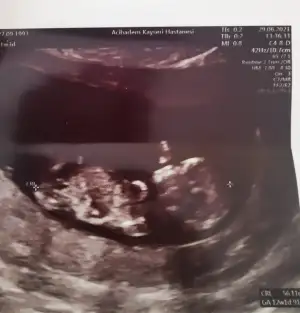

Kız görünüyor11+2 bı tahminde bulunur musun canım Eki Görüntüle 2894305

Kız gibi sanki

Yaa inşallah canım bu usg ablaminki ve 2 oğlu var doktor da demiş umitlenme ama kız gibiKız görünüyor![]()

Kaç haftalık USG 11 12 13 haftalar olmalı nub görünmüyor başka USG varsa